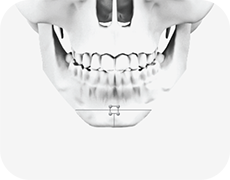

01

턱의 끝부분을 T자 모양으로 절골

-

02

절골한 뼈의 가운데 부분을 제거

-

03

절제 된 양쪽의 뼈를 모아 가운데 고정

-

04

사각턱을 포함한 튀어나온 부분의 뼈를 절제

-

05

절제한 양쪽의 뼈를 제거하여 V라인 턱이 완성